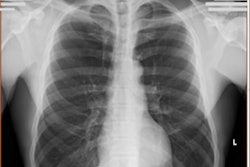

Through DocPanel, imaging centers can use the radiologists to interpret images from specific areas of the body.